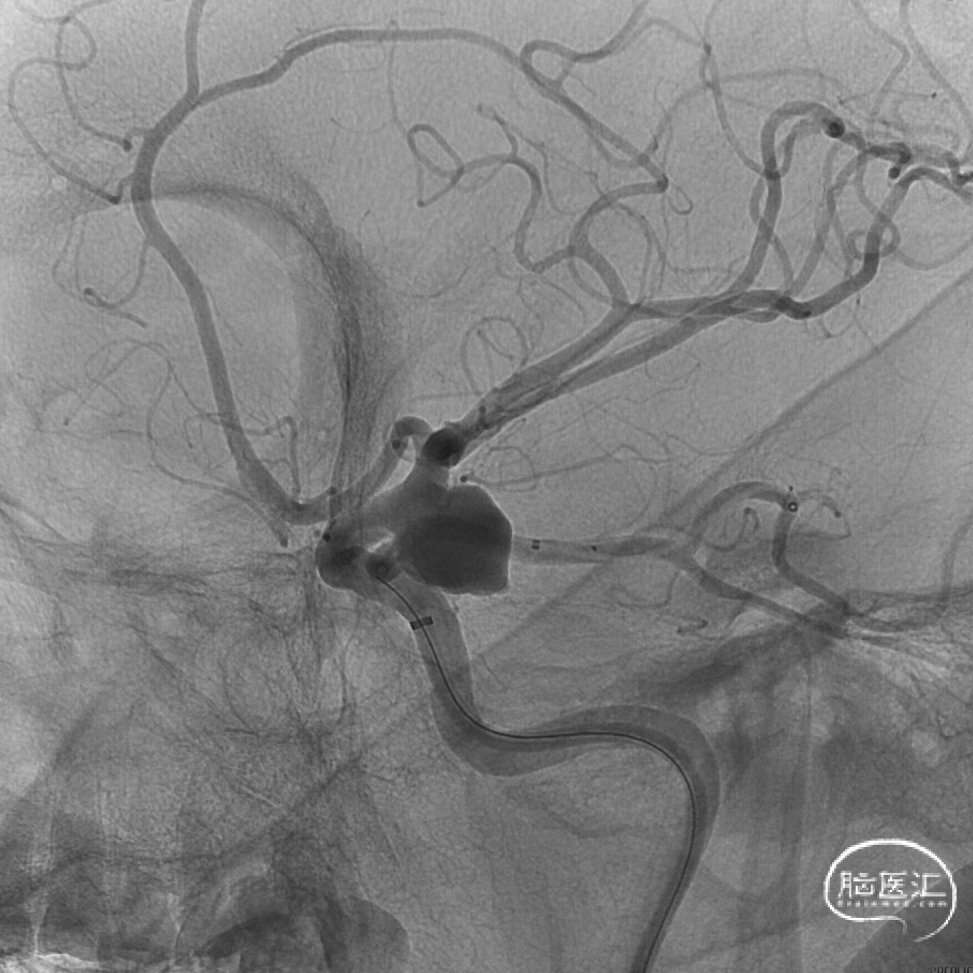

3D造影。

“回马枪”技术虽然并不是栓塞颅内动脉瘤的一种常用的技术,但其在处理一些特殊的动脉瘤有着得天独厚的优势。

“回马枪”技术的塑形并不是单一的,可以根据需要灵活调整。

“回马枪”技术也可以辅助一些锐角分支的处理。